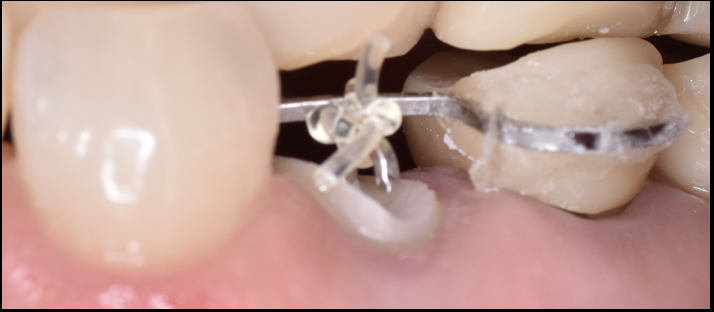

【池袋 歯医者】被せ物のトラブルを防ぐ!クラウン...